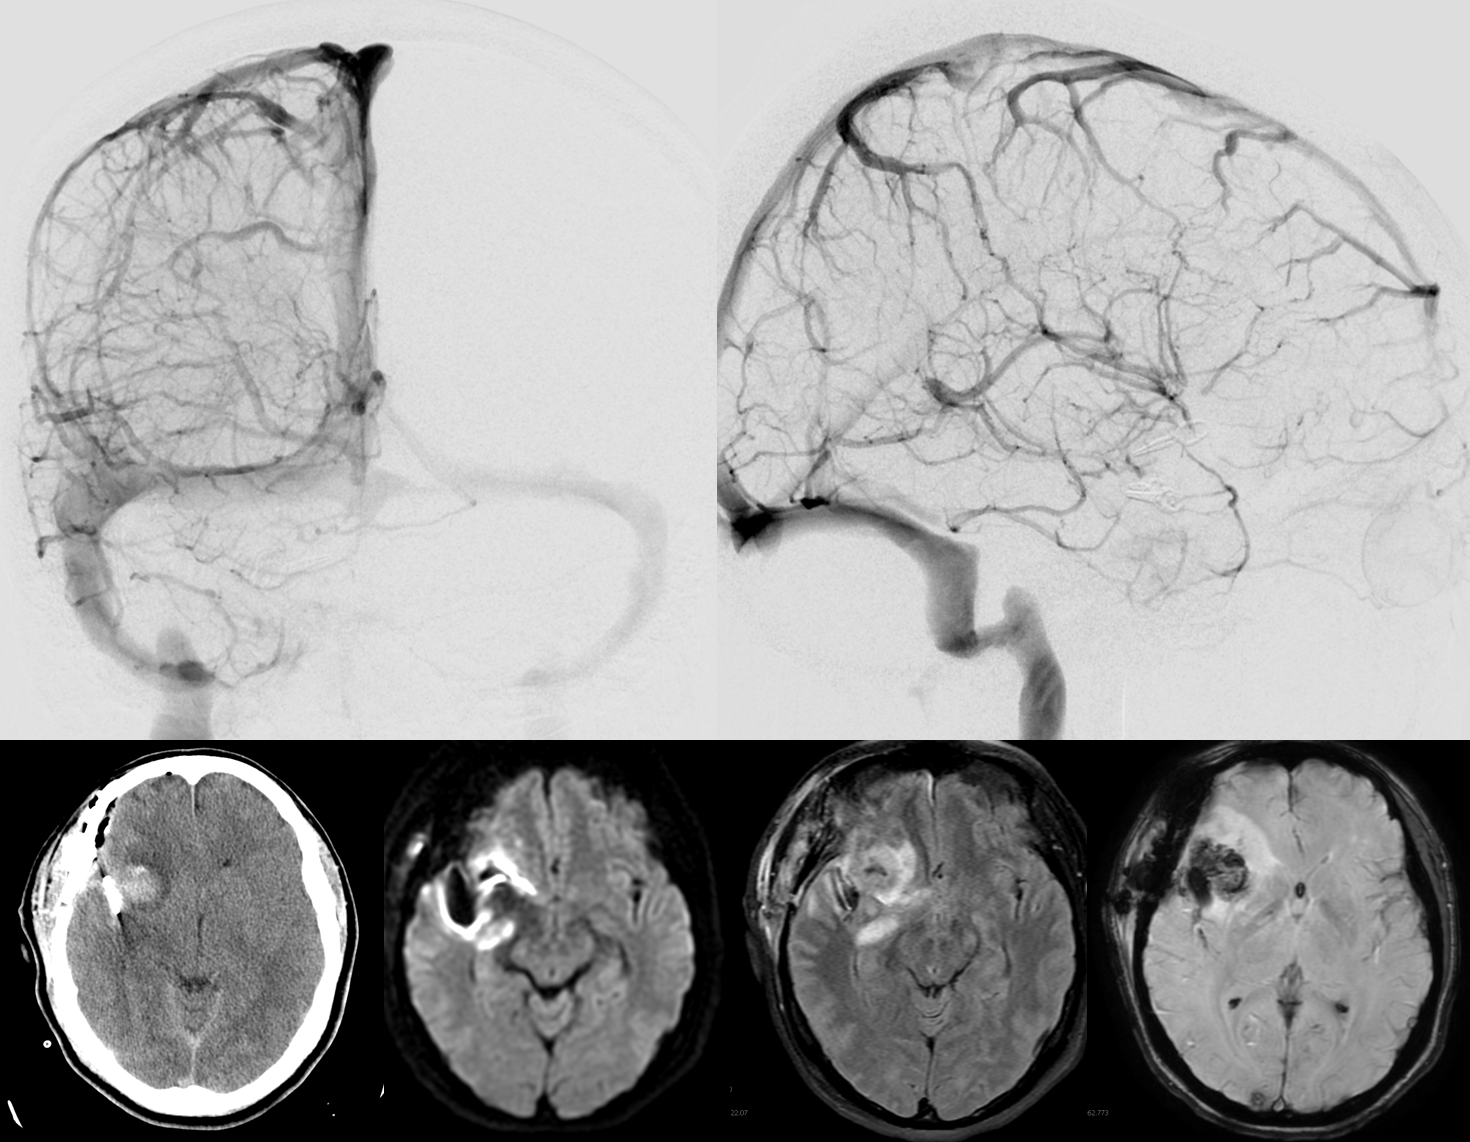

Sometimes, its good to get an angio when you are at a loss about something that might be vascular — bleeding, for example. Here is a young man with spontaneous left temporal lobe hemorrhage. MRI shows no evidence of AVM, aneurysm, or any other problem. In our book, this needs an angio

MRI (hemoflash and T2, and CT images of left temporal hemorrhage). Note to radiologists — please don’t ask to see the whole study — there is nothing suspicious there, believe me.

Angio of the same patient — what is the diagnosis?

Cerebral venous thrombosis. Isolated thrombosis of the inferior temporal vein/vein of Labbe. Notice irregular and thinned appearance of inferior temporal gyrus vein (dark blue arrows), compared with the larger caliber of the same vein anteriorly (purple) and posteriorly (light blue), which is the vein of Labbe.  Other signs are:1) There are no normal veins seen draining the temporal convexity — this cannot possibly be normal. Deep sylvian veins and striate veins are there (unlabeled, see venous system for clarification) If you do enough angio, you will recognize that this appearance is very abnormal. Every other lobe has juicy veins, for example 2) There is evidence of temporal lobe congestion, which is somewhat subtle, but present — in the inferior and superior temporal regions. The middle “layer” of the temporal lobe is hypovascular — corresponding to location of the clot — its a hyperemia-clot-hyperemia sandwich.

As usual, cerebral venous thrombosis can be an elusive diagnosis — especially if the sinuses are not involved. But it certainly happens, and certainly more often than is known about.

stereo pair of the same patient, can’t resist having one. Notice hyperemia adjacent to congested inferior temporal lobe vein, and clot-related lucency above it.

Venous Thrombosis Case 2

This patient with Sickle Cell Disease presented with headache. Â CT identified subarachnoid hemorrhage over the convexity (red arrows). Â The subtle hyperdensity adjacent to the left inner table was not appreciated initially (pink arrows).

The patient was referred directly for angiography to look for the cause of subarachnoid hemorrhage. Â Frontal and lateral projection digital subtraction angiographic views of the left ICA injection, in venous phase, demonstrate abrupt cutoff (pink arrows) of the vein of Labbe. Â “Tram-track” sign of filling defect in the vein is acually seen on the lateral image (yellow arrow). Â The venous sinuses are fully patent.

Subsequently obtained contrast MRI demonstrates nicely the hyperintense thrombus on sagittal T1-weighted imaging, and the intraluminal thrombus is seen on post-contrast T1-weighted images (yellow arrows). Again, the sinuses are patent (green arrows). Â Patients with sickle cell disease are, of course, at major risk for sickling, leading to both arterial and venous thrombosis.